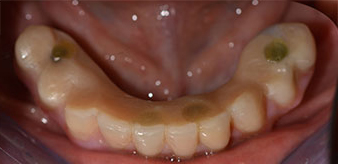

La patiente âgée de 64 ans présente une denture résiduelle des dents 38, 33 et 43 et une prothèse amovible mandibulaire stabilisée par crochets (Fig. 1 et 2).